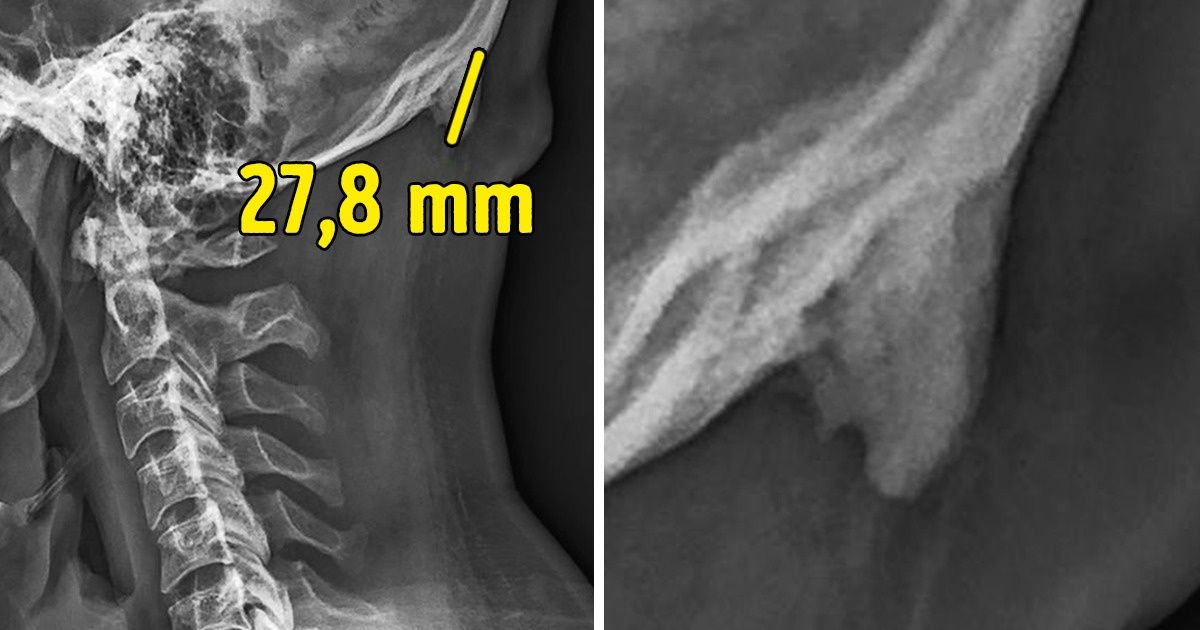

Ces scientifiques ont développé un studio dans lequel ils ont réalisé des radios de la tête et du cou d’environ 1 200 personnes entre 18 et 86 ans. Les images ont prouvé qu’au moins un participant sur trois, jeunes pour la majorité, possédait cet os en forme de corne au niveau de la partie basse du crâne. Elle était appelée “protubérance occipitale externe” et dans certains cas, elle était tellement grande qu’elle pouvait mesurer plus de 3 cm de longueur, ce qui permet de la voir et de la sentir à travers la peau.